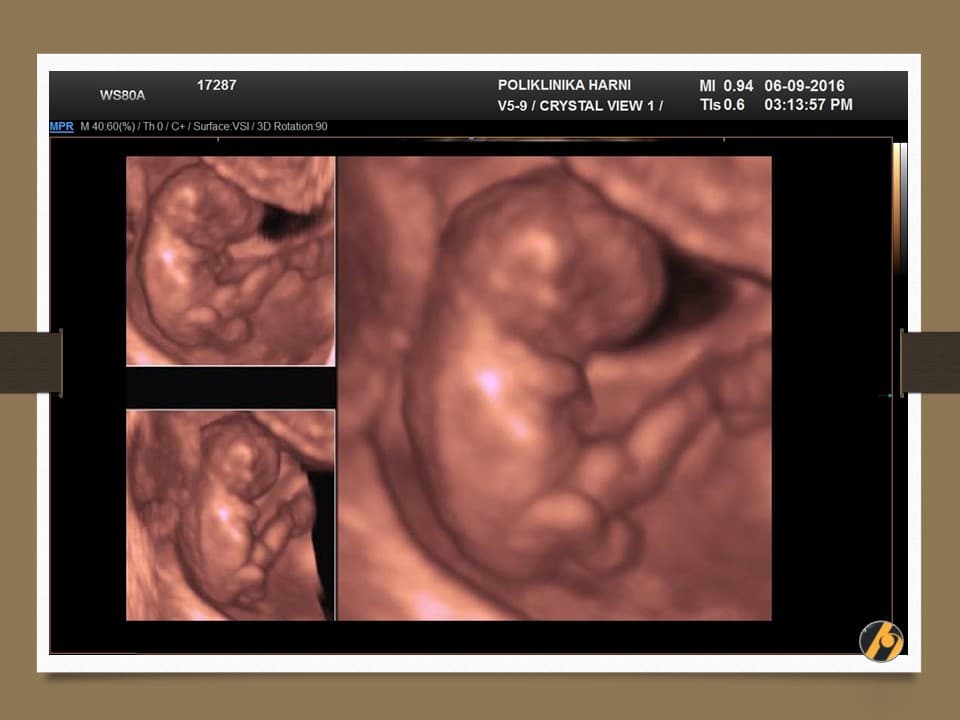

Glava vaše bebe još uvijek svojom veličinom nadmašuje tijelo, i čini gotovo cijelu polovicu dužine tijela. Razlog tomu je veoma rani početak razvitka mozga. Sada se uši postupno premještaju od vrata prema njihovom mjestu na glavi.

Napreduje razvitak ostalih organa. U trbuhu se intenzivno razvijaju crijeva, koja se nerijetko mogu vidjeti ultrazvučno i u pupčanoj vrpci / fiziološka omfalokela što je za ovaj period embriogeneze sasvim u redu. Crijeva se tijekom narednog tjedna vraćaju sasvim na svoje mjesto, u trbuh.

Vaša beba dugačka je 4.5 - 6.0 cm, a teška je 8 - 10 g.